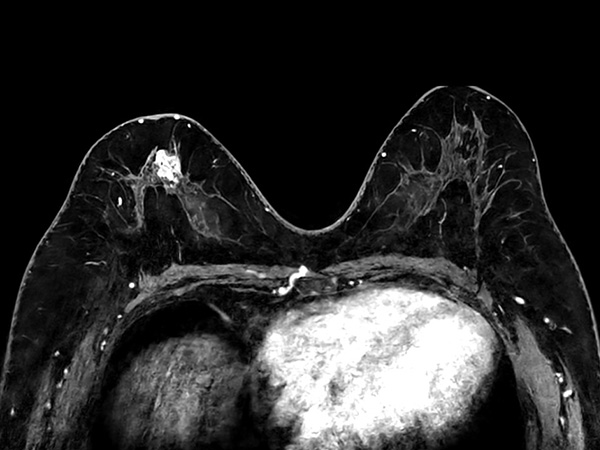

Axial T2w TSE